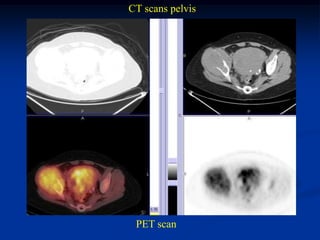

Case #1182.1 Metastatic leiomyosarcoma from uterus to hip

Axial T-2

57 yr female with hip pain 3 months               Cor PD

CT scans pelvis

PET scan

CT scan chest